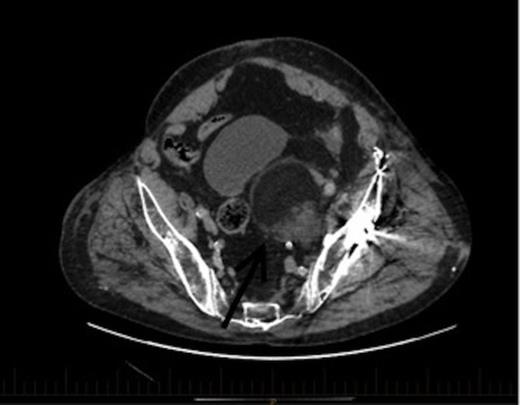

CT coronal view of the lesion demonstrating compression of the bladder. Arrow denotes the EMH lesion

A CT scan demonstrated a 6.7x6.3cmx7.3cm well-defined left pelvic mass immediately medial and adjacent to the left acetabulum compressing the bladder and the iliac vessels. The mass was heterogeneous in density comprising of both muscle and fat with no calcifications. He underwent a repeat staging-CT, MRI, whole body thallium scan, and a CT-guided biopsy. The MRI scan confirmed a lobulated well-circumscribed mass with a heterogeneous T1 and T2 appearance. Areas of hyperintensity reported on CT corresponded to fatty components within the mass, while the rest of the mass appeared relatively hypointense to skeletal muscle, and was thought to be consistent with a liposarcoma. The Single Photon Emission Computed Tomography (SPECT) scan demonstrated low-grade activity in the mass and the staging-CT did not reveal any signs of malignancy. A confirmatory CT-guided biopsy however diagnosed the mass as EMH tissue, while a CT angiogram demonstrated no external compression of the iliac vessels.

This patient was subsequently discussed at a multidisciplinary meeting, where it was decided that in view of the urinary symptoms and his high operative risk, the mass should be treated with CT-guided radiofrequency ablation using a multi-lined electrode. However, the patient declined treatment and was temporarily lost to follow up after moving interstate. Two years later, he presented to the hospital with bowel obstruction secondary to an incisional lumbar hernia, and the follow up CT scan (Figures 2 and 3) revealed no increase in the size of the mass, and repeat biopsy re-confirmed the presence of EMH. His urinary symptoms remained stable.